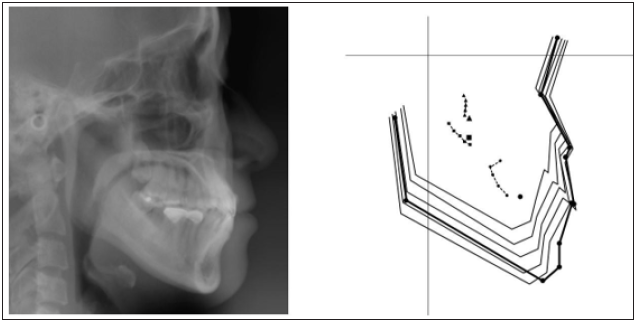

2). Cephalometric analysis indicated that this patient had a skeletal. Class I pattern with

an ANB angle of 3.4 ° with a mean mandibular angle. The upper incisor positions showed

tendency of mild retroclination measured from U-1 to A-P plane of 5.3mm. The mandibular

incisors were retroclined as compared to norms (Figure 3 & Table 1).

Figure 3:Initial Cephalometric radiograph.